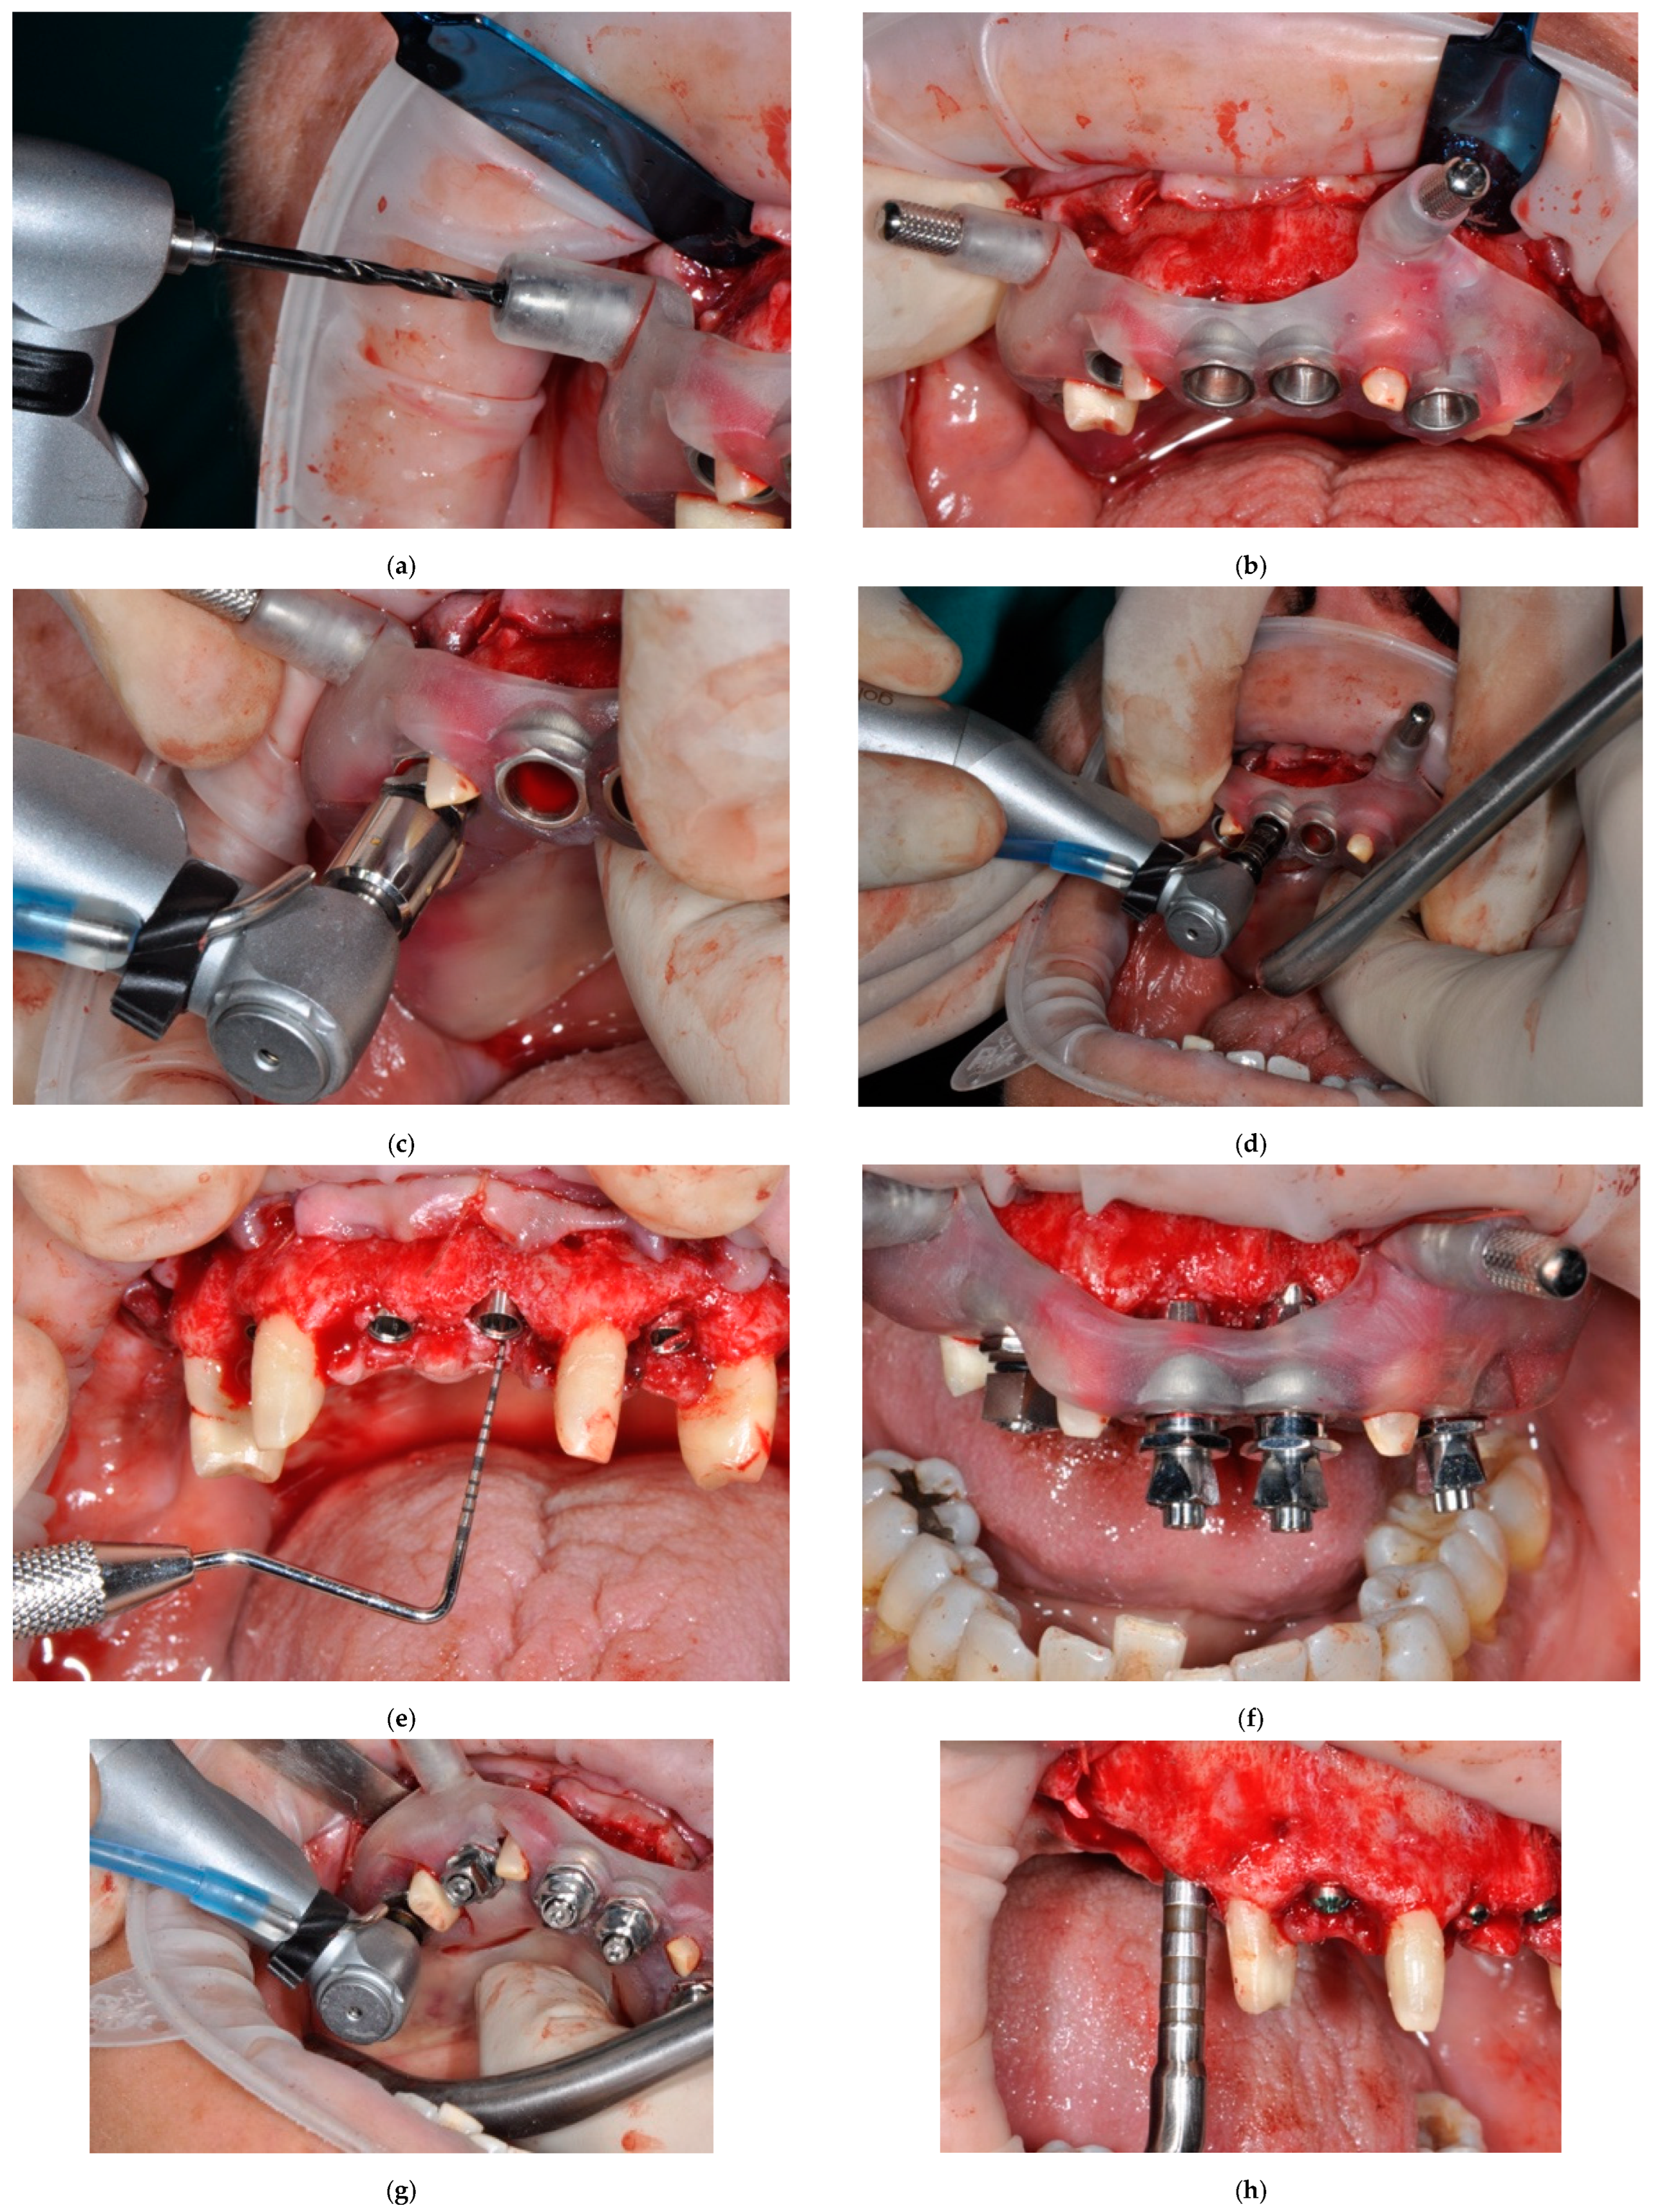

2. Materials and Methods

2.1. Surgical Phase

2.3. Surgical Phase: Insertion of the Implants